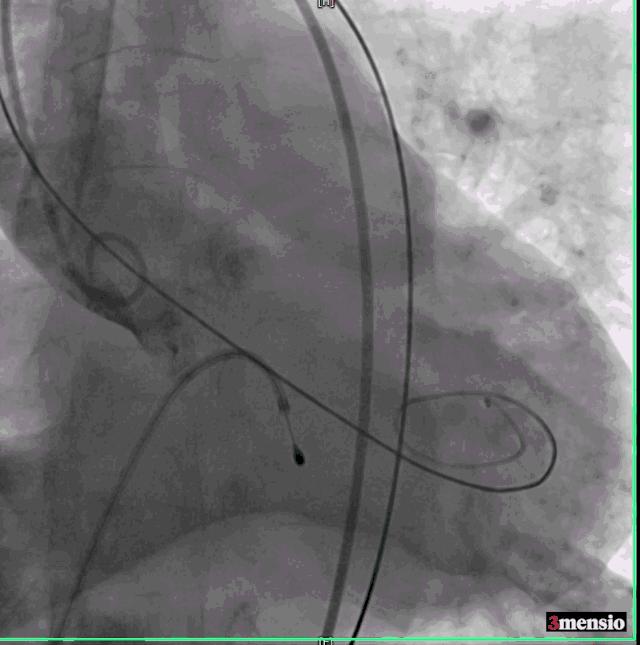

交换Amplatz Super Stiff导丝,再送猪尾导管至左心室,测量左室压力142/6mmHg,升主动脉压力254/58mmHg,跨瓣压差112mmHg,交换Amplatz Super Stiff导丝至左室,撤出猪尾导管,在临时起搏器控制性降压下用20mm球囊扩张主动脉瓣。

球囊扩张

危险在此时发生了,球囊扩张后,患者出现血压下降,造影发现钙化的瓣膜扩开后出现大量反流,手术团队当即决定马上植入已经预装好的23号瓣膜,且因为预扩张球囊的反馈情况,把原有定额17ml减少2ml至15ml,成功跨瓣后精确定位并在临时起搏器180次/分起搏控制血压下于高位释放,过程顺利。

球囊扩张后重度返流